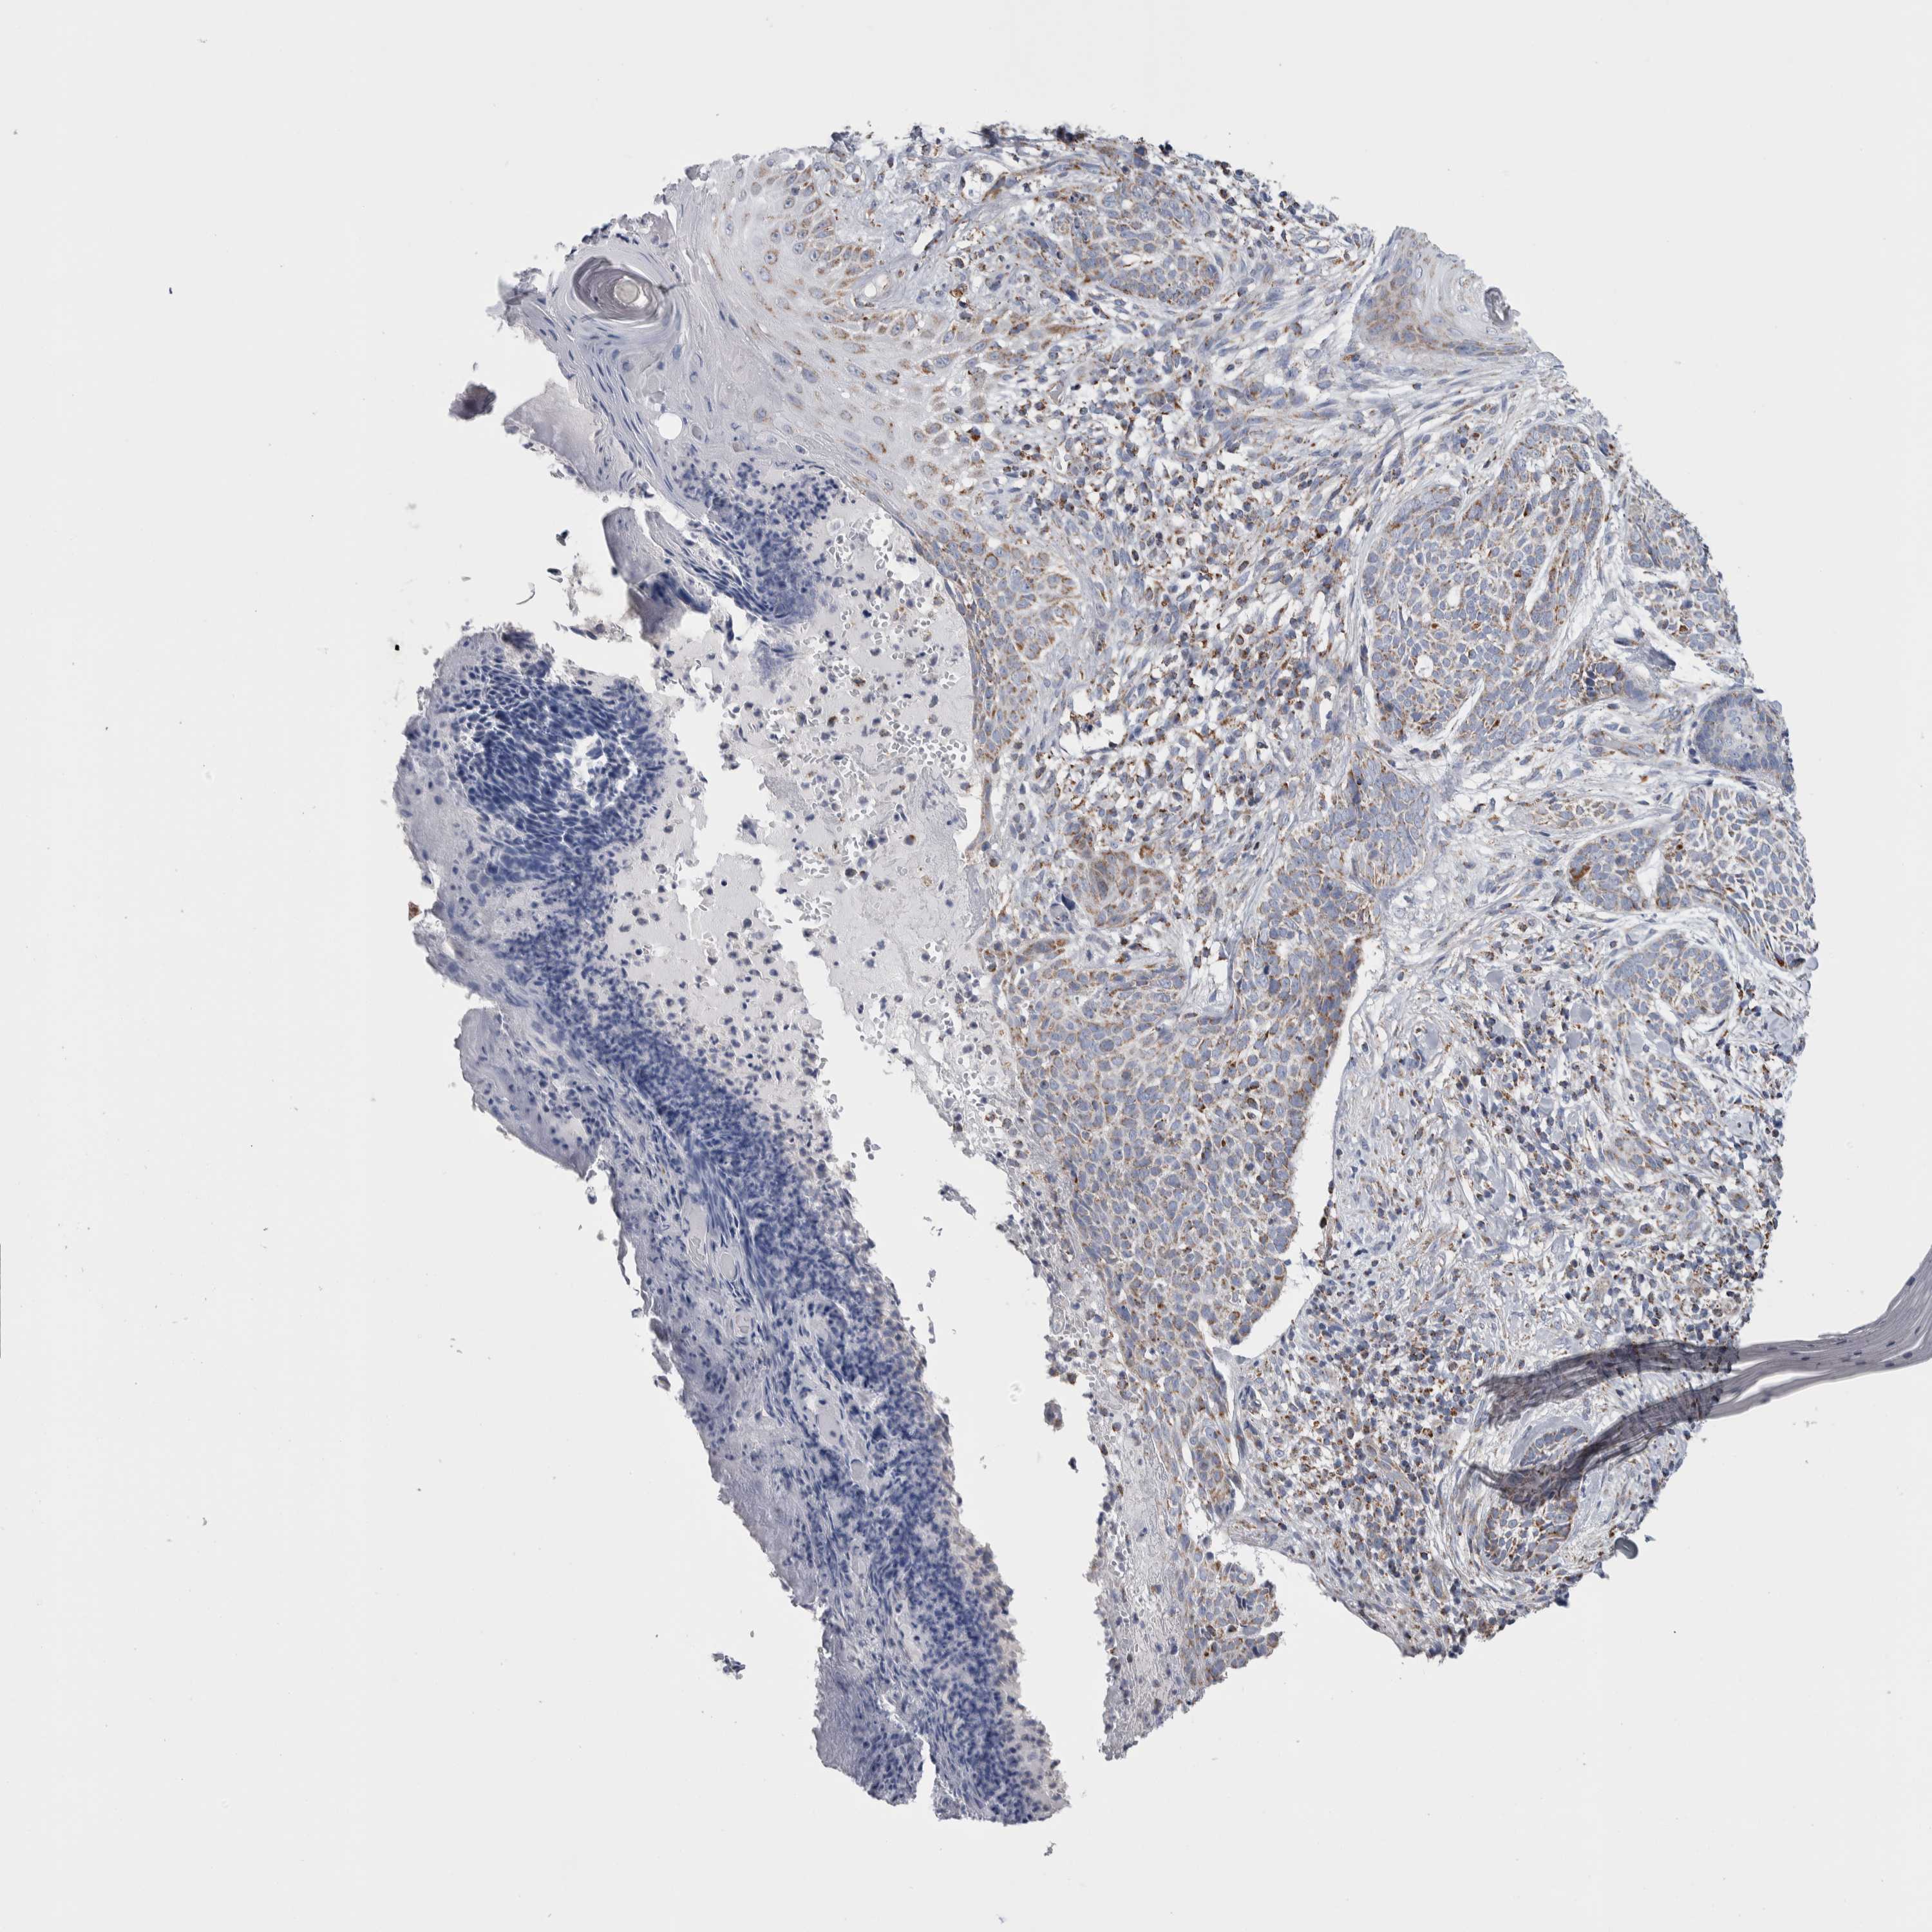

SKIN CANCER - Protein expressioni

A mouse-over function shows sample information and annotation data. Click on an image to view it in a full screen mode. Samples can be filtered based on level of antibody staining by selecting one or several of the following categories: high, medium, low and not detected. The assay and annotation is described here.

Each image is clickable and will lead to virtual microscopy that enables deeper exploration of all samples and also displays staining intensity scores, fraction scores and subcellular localization as well as patient and tissue information for each sample.

Antibody HPA018993

Squamous cell carcinoma, NOS